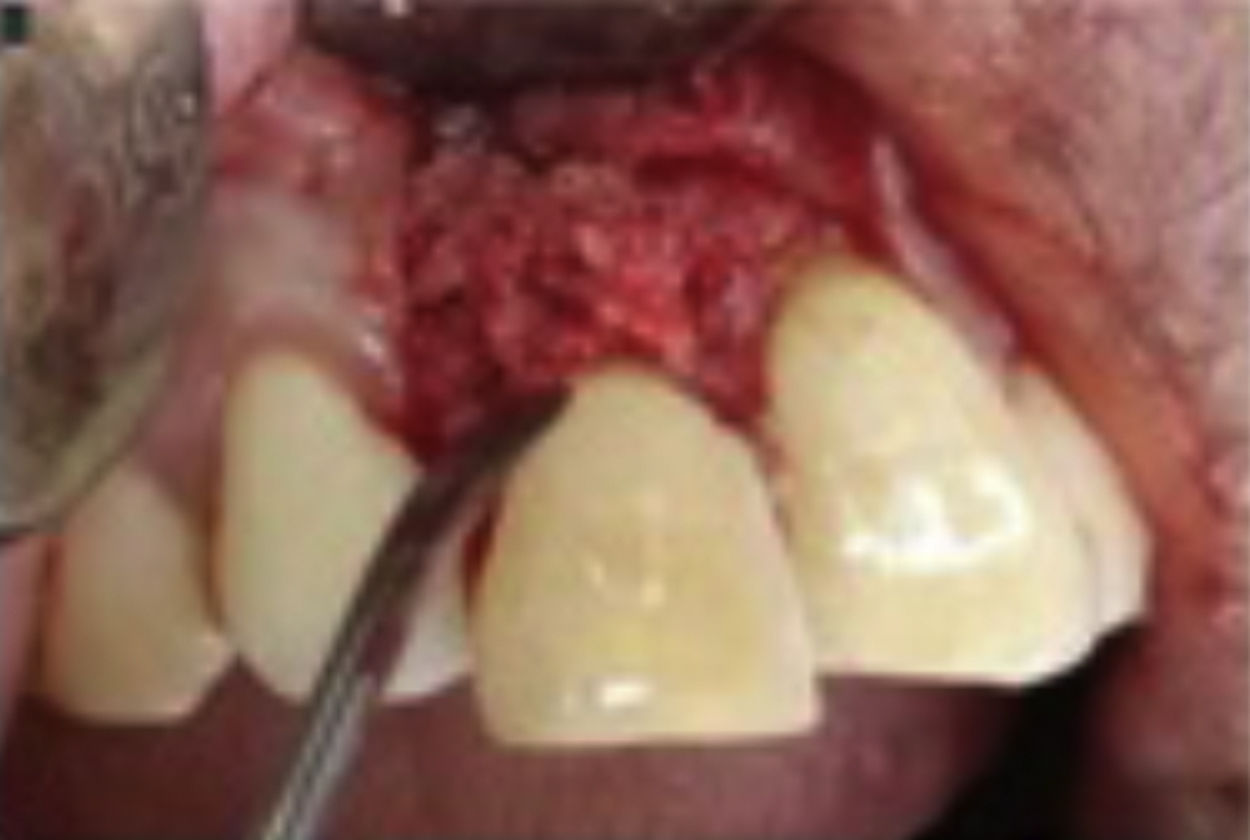

In the surgical procedure, extraoral and intraoral disinfection were performed with a 2% povidone-iodine solution (Fig. 3) then infiltrated local anesthesia with lidocaine HCL anesthetic and epinephrine 1:80,000 (Fig. 4) was administrated. Sulcular and vertical incisions were performed using no.15 blade (Fig. 5) and the flap was exposed using a rasparatorium (Fig. 6a and b).

Curettage of granulation and necrotic tissue was carried out using Gracey curettage and followed with root planing (Fig. 7a–c).